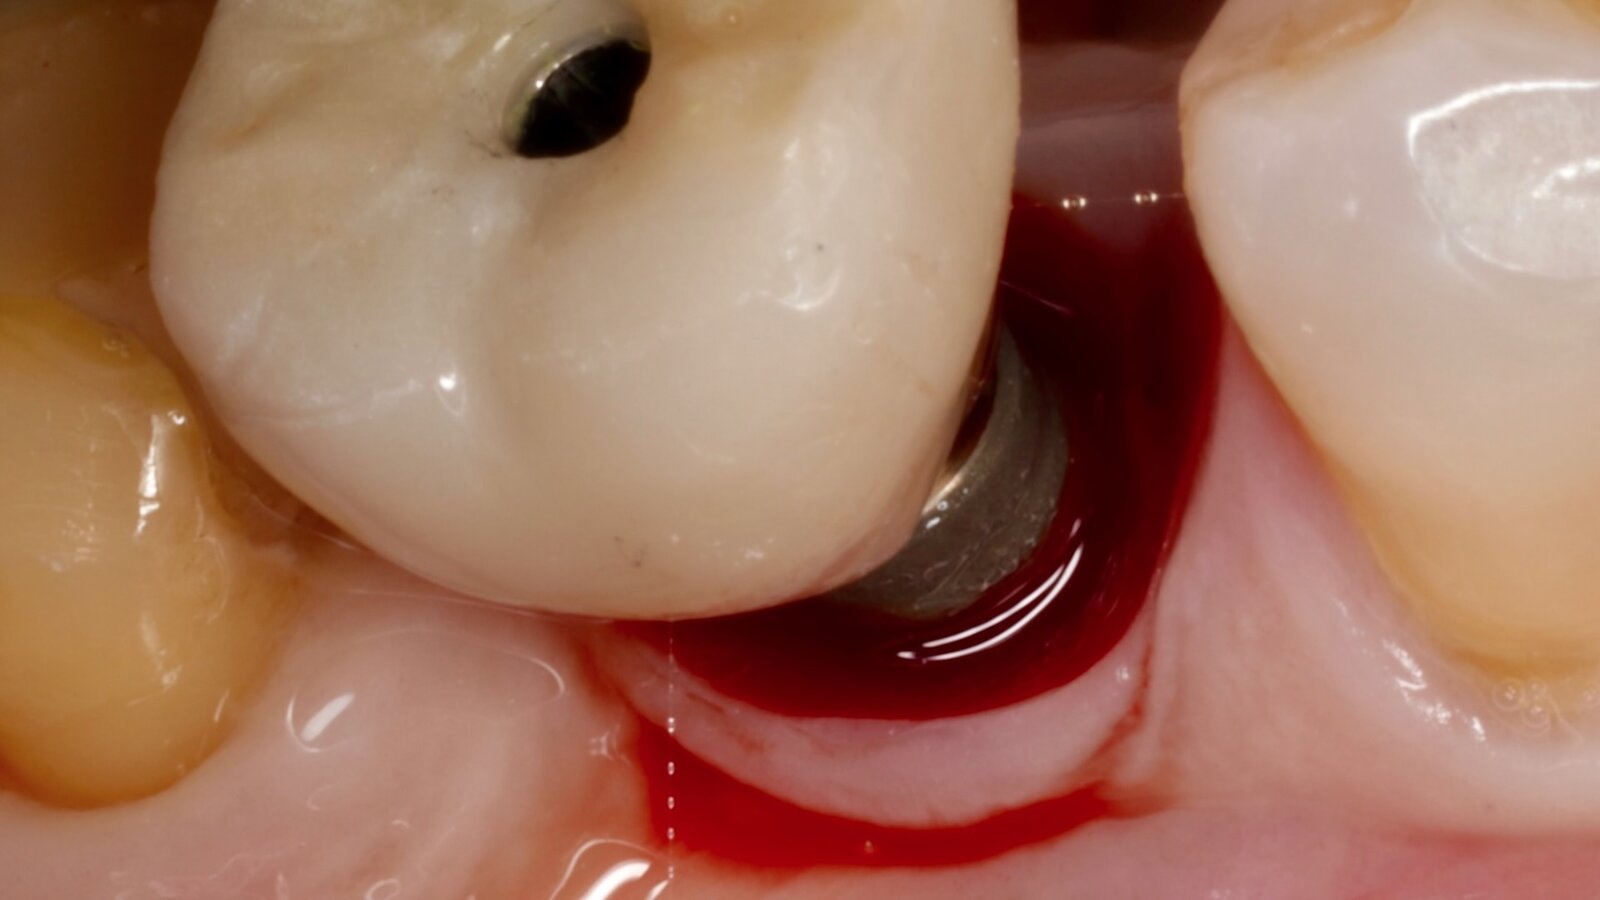

Figura 1. Evidencia clínica de periimplantitis en un paciente con diabetes mellitus tipo 1. Imágenes: Iván Herrera

La periimplantitis es una enfermedad inflamatoria crónica que afecta los tejidos blandos y duros que rodean los implantes dentales osteointegrados. A pesar de los elevados índices de supervivencia reportados para los implantes dentales, la creciente prevalencia de las enfermedades periimplantarias ha generado una preocupación sustancial en la práctica clínica que se refleja en la literatura científica contemporánea. La evidencia actual respalda un modelo etiopatogénico multifactorial en el que la interacción entre el biofilm bacteriano, los factores locales asociados al diseño protésico y las condiciones sistémicas del paciente determinan la progresión de la enfermedad periimplantaria (Figura 1).